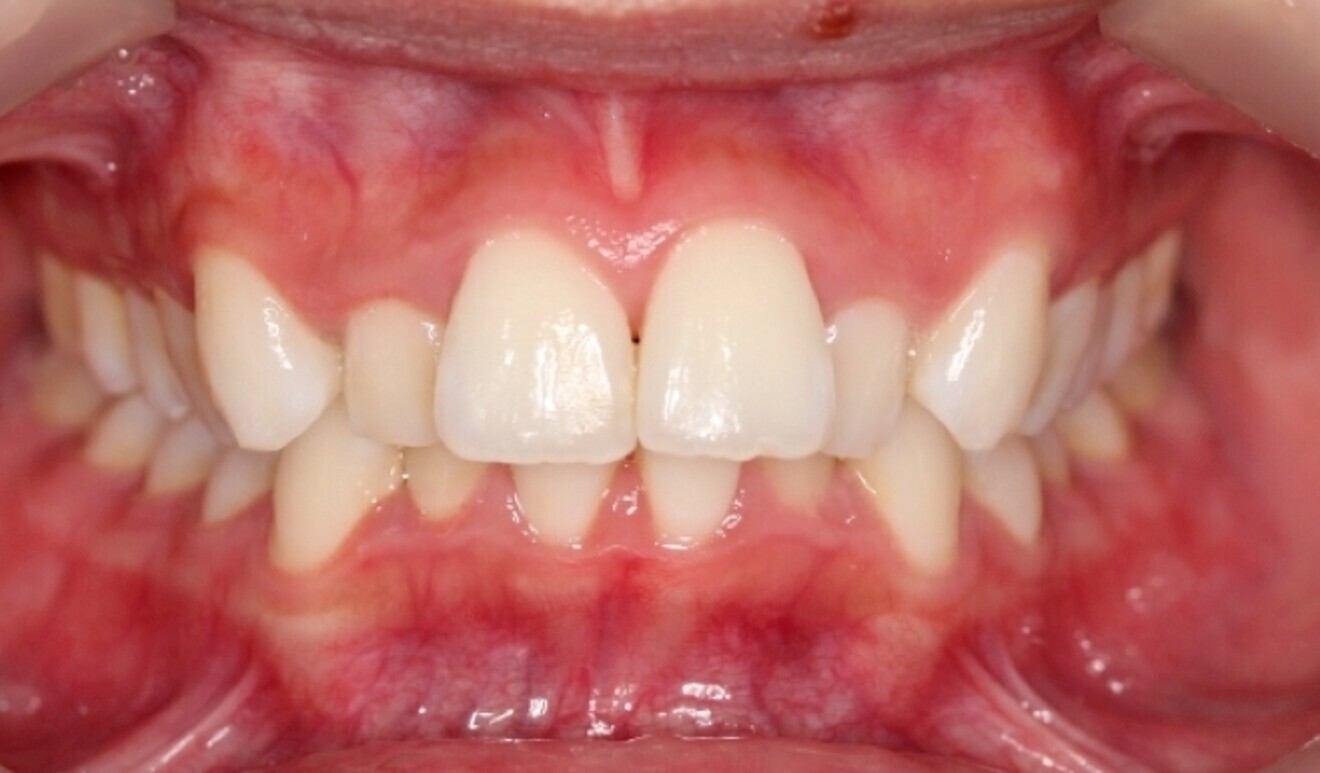

Fig. 2

The starting point for Oratomic4D was selecting a real patient to replicate. After an extensive search, the patient, Tina, was chosen for her ideal oral anatomy and range of treatments that could be simulated. Unlike a typodont model, Tina had mild crowding, impacted maxillary and mandibular third molars, and complex root canal anatomy (Figs. 2–7).

These irregularities in Tina’s oral anatomy made her an ideal candidate for the creation of a range of realistic simulation models that are highly representative of the types of patients encountered in dental practice.

Combining Tina’s intra-oral scans and CBCT data along with Oratomic4D’s internal design and manufacturing processes, the company was able to accurately replicate her jaws, bone structure, ligaments, teeth and root canals on a 1:1 scale using Asiga printers.